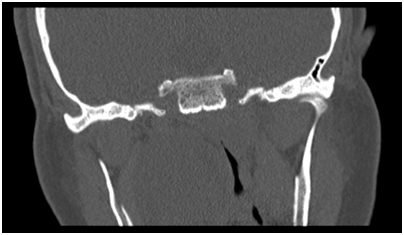

Figure 3 Intra-operative photograph at the start of surgery with large palatal lesion.

A transoral approach was used using a Boyle Davies gag and cheek retractors to aid with ac-cess and exposure. Cheek retractors proved to be handy for better exposure. The lesion was 4 x 5 cm in diameter, partly cystic and unfortunately the capsule was breached during the ma-nipulation of the tumour. After resection, the defect was closed primarily with absorbable su-ture in an interrupted fashion (Figure 4) (Figure 5).